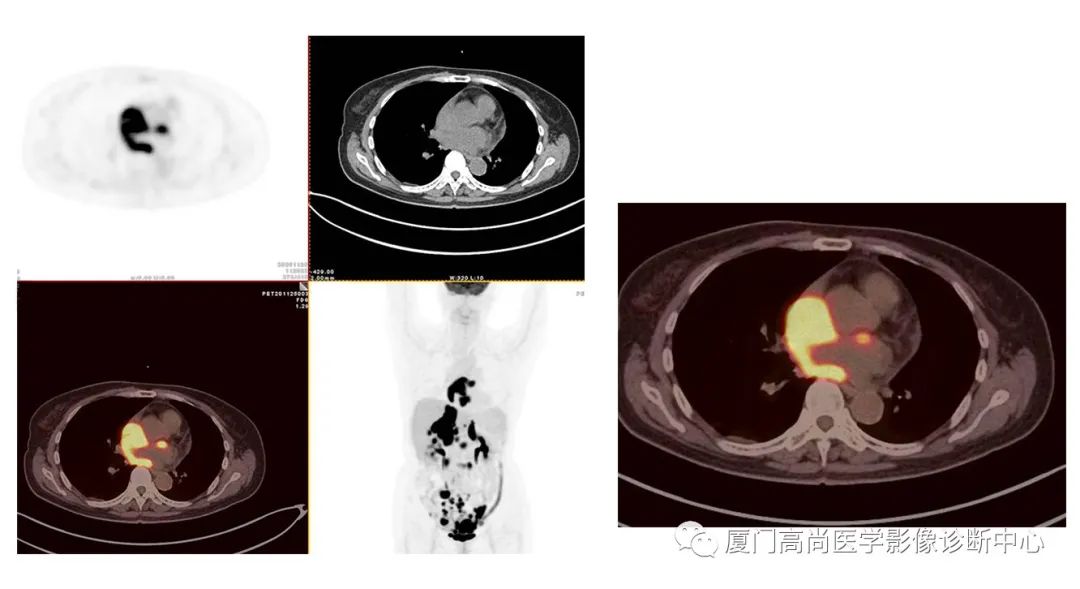

病例2、某女士,62歲,近3個月來自覺消瘦,無其他自覺癥狀,CT發(fā)現(xiàn)雙側(cè)腎上腺增大,性質(zhì)待定,查血各項腫瘤標(biāo)記物均正常,臨床診斷不清,申請做PET/CT檢查

左心房淋巴瘤病灶

右心房淋巴瘤病灶

雙側(cè)腎上腺病灶、膽囊病灶

腹腔淋巴結(jié)腫大

小腸多段淋巴瘤病灶

PET/CT發(fā)現(xiàn) :左心房、右心房見團塊狀FDG攝取增高;雙側(cè)腎上腺增大,F(xiàn)DG攝取增高;膽囊和胃壁結(jié)節(jié)樣FDG攝取增高;小腸多節(jié)段腸壁增厚,F(xiàn)DG攝取增高;腹膜后、腹腔及盆腔多發(fā)淋巴結(jié)腫大,F(xiàn)DG攝取增高;上述考慮為淋巴瘤

經(jīng)腎上腺穿刺活檢 :病理證實為彌漫大B細胞淋巴瘤